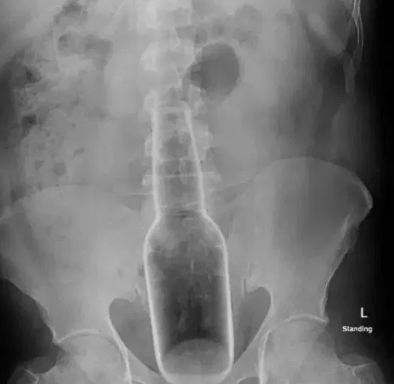

The doctor then found a hard substance in his rectum and instantly asked him to get an X-ray done.

He went for it and they found out a traditional mosquito replete liquid’s bottle inside of him. The bottle was 7 inches long and 2 inches wide.